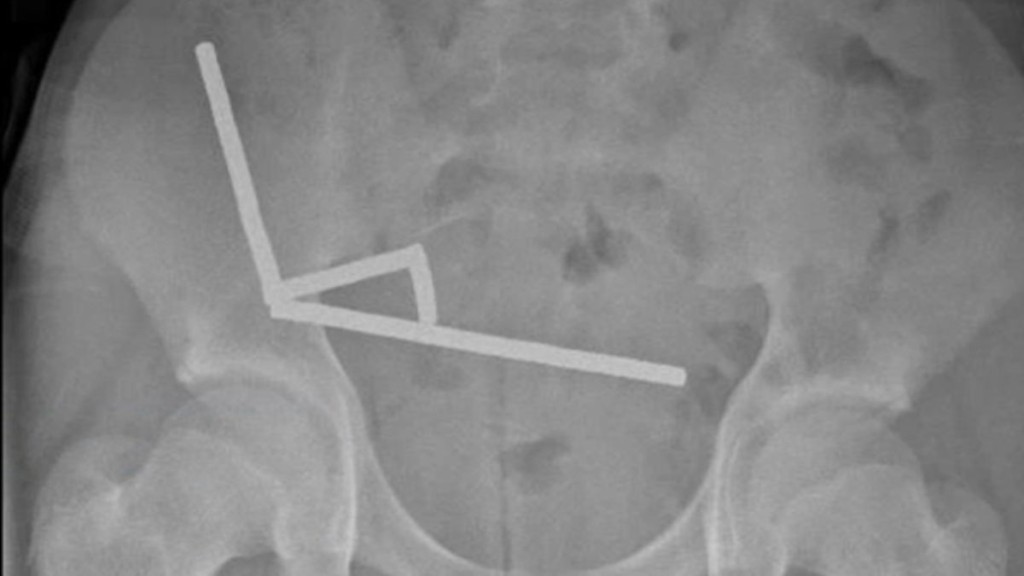

外科醫生透過手術移除壞死組織,並取出磁鐵。新西蘭醫學期刊

醫生指出,磁鐵造成的壓力導致男童的小腸及盲腸有4處組織壞死。

外科醫生其後透過手術移除壞死組織,並取出磁鐵,該少年在住院8天後出院,已返家休養。